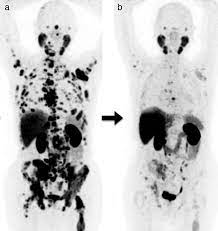

Nöroendokrin tümörlerde, Ga-68 DOTA-TATE PET/BT ile tümöral dokuların yüksek hassasiyetle ve özgüllükle görüntülenebildiği bir durumda, Lu-177 DOTA-TATE ile bu tümöral dokuların spesifik ve hedefe yönelik bir şekilde tedavi edilebildiği vurgulanmaktadır. Bu, teranostik uygulamalar açısından büyük başarı ve yenilikçi bir yöntem olarak kabul edilmektedir.

Yapılan araştırmalar, DOTA-TATE’in NET hastalarında yaşam beklentisini artırabileceğini, genel yaşam kalitesini iyileştirebileceğini ve semptomları hafifletebileceğini göstermektedir. Bu tedaviyi düşündüğümüzde, hastaların tümör ve metastazlarının somatostatin reseptörlerine olan pozitifliğini belirlemek amacıyla Ga-68 DOTA-TATE PET/BT taraması yapılmalıdır.